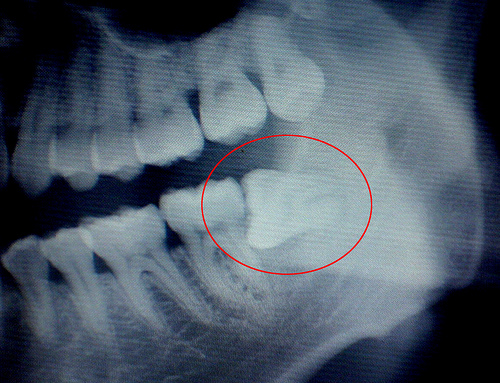

我长“智齿”拉!# L7 Y) }( Q( f

天,不用怀疑,我说的就是我!知道什么是“智齿”不?老人言,智齿就是代表长大了真正成熟了,这时候就会长一颗牙齿叫做智齿。。。一般在二三十岁的时候,当然也有四十多才长的。。。

就这样,俺晓得了这是要长牙了。其实我老新奇的,我都二十好几了,居然还长牙齿,哈哈。难道返老还童了?。。。。一路欢歌到公司。! m" q5 n, P/ z0 R4 N

4 }. \( n( a3 m0 I8 J% D# r* q" }) \ 这症状吧,刚开始还好,这不,一天下来,越来越疼了,到了今天,咽口口水都疼啊。。。哎。。。

跑到隔壁问四十多的邻居大姐,人家到底是过来人!耐心解释,说我这是代表成熟了的智慧的牙齿!( w! {# Z' k" b% N. y8 X

5 Y, {. d) V5 _* c7 g 哦,老天啊,敢情我这才成熟啊。。。哎,原来成熟也是需要付出代价的啊!好疼啊,疼的我吃不下饭!洗个冬枣吃吃,这么小一个东西,我居然吃不到半个,实在是难以下咽啊——疼!6 o7 w5 M3 {1 N! M2 l2 d

. R6 K9 g2 r p# y# H# W 恩,我这智慧的牙齿啊,请你老人家快快长出来吧!据说你要是再不长出来我还得到医院去,在牙龈肉上割个口子让您老人家出来!哦,我的天,这怎么跟女人生小孩剖腹产一样痛苦和令我感到害怕啊?我汗。。。太辛苦了。。。555。。。。。。

哎。。。。我疼啊疼,智齿啊,快点出来吧!欢迎你来到人间(无奈的表情)。。。